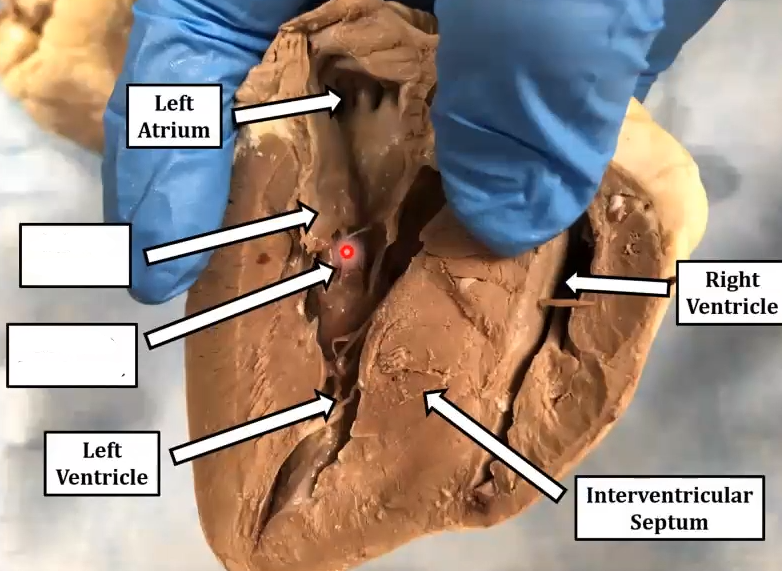

3. left atriumright ventricle

interventricular septum

left ventricle

2. Bottom

Mitral valve

Chordae tendinae